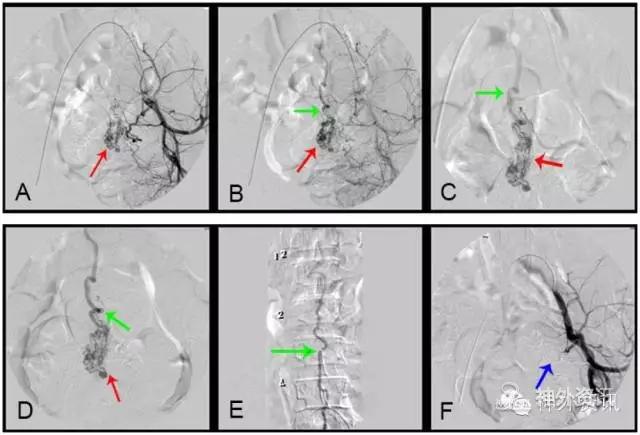

图10: L3髓周动静脉瘘,↑示瘘口。

③经股静脉穿刺插管进入上腔静脉、下腔静脉,分别将造影导管超选择逆行插入奇静脉、半奇静脉、副奇静脉与腰1~4橫静脉[9],注入非离子造影剂(5ml/s、总剂量7ml),了解这些静脉有无向下腔静脉回流障碍,导致脊髓静脉高压综合征。如这些静脉有狭窄、闭塞,或造影剂不能向上、下腔静脉回流时,就返流经椎管内静脉回流至脊髓表面正常引流静脉,引起脊髓静脉高压综合征,导致脊髓功能受损(图14)。

图14: 第三腰横静脉狭窄致脊髓静脉高压综合征A~C. MRI,红色↑示血管流空影;D、E. 第三腰横静脉造影,红色↑示左第三腰横静脉狭窄,绿色↑示向下腔静脉回流少,蓝色↑示向脊髓静脉回流;F. 球囊扩张治疗第三腰横静脉狭窄致脊髓静脉高压综合征,黄色↑示扩张球囊;G. 球囊扩张后,黑色↑示狭窄腰横静脉向下腔静脉回流通畅。